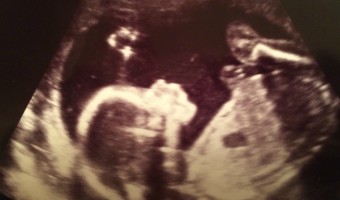

Mommy & Me: Half Baked!

I'm officially half-baked! Or, at least the bump is. Last week marked the halfway point of my pregnancy, and I can't believe I'm already this far in. My belly has absolutely grown overnight, and we've just learned the gender! (I made a little video I plan on posting soon - so you'll have to wait … [Read more...]